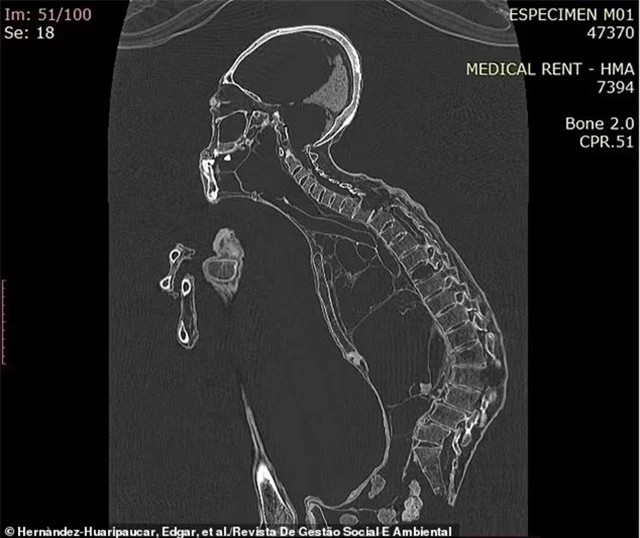

Nghiên cứu được công bố trên Tạp chí Quản lý Xã hội và Môi trường có đoạn :'Đặc điểm đáng chú ý nhất của hộp sọ là sự kéo dài đáng kể, không có dấu hiệu chèn ép hộp sọ từ các tác nhân bên ngoài. Cụ thể, phần vòm sọ có sự phát triển và tăng trưởng bất thường, giống với kiểu hình đầu dài. Ngoài ra, thể tích hộp sọ lớn hơn 30 phần trăm so với hộp sọ của người bình thường.'

Kết quả quét bên trong sinh vật cho thấy nó có đôi mắt lồi và hàm trên và hàm dưới nhô ra. Maria bị mất sáu chiếc răng và những chiếc còn lại đã bị mòn nghiêm trọng - ba chiếc răng khôn cũng bị mất.

So với bàn chân người bình thường, xương gót chân của Maria có hình dạng và cấu trúc khác biệt. Thông thường, xương gót chân của con người có một khối u lớn ở phía sau giúp nâng đỡ trọng lượng cơ thể và giữ thăng bằng khi đứng thẳng trên hai chân. Tuy nhiên, tượng Maria lại thiếu một khối u lớn, điều này cho thấy Maria đã khom lưng khi đi để giữ thăng bằng.

Phân tích hình ảnh cũng xác định sinh vật này bị viêm khớp ở tay và chân, cùng với tổn thương cột sống. Các nhà nghiên cứu đã viết:'Dựa trên các đặc điểm hình thái - giải phẫu của cấu trúc xương chậu, mẫu vật M01 tương thích với xương chậu phụ và tương ứng với một cá thể nữ'.

'Dựa trên phân tích hình thái bề mặt và hình ảnh cắt lớp, có thể kết luận rằng mẫu vật M01 là một cơ thể người khô có cấu trúc sinh học tương tự như con người, nhưng lại có nhiều điểm khác biệt về cấu trúc và đặc điểm giải phẫu cũng như hình thái.'